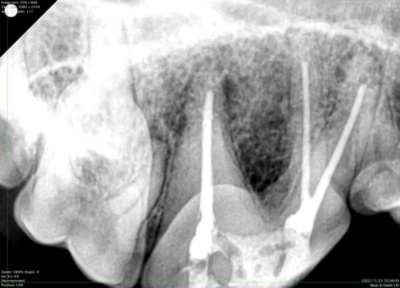

レントゲン検査検査。根っこの周囲にある黒い部分が病変(オレンジ転線部分)

金属の棒(ファイル)を歯髄に挿入し、長さをレントゲンで確認しているところ

青いシートがラバーダム。周囲をコーキング材で埋めている。3本の歯髄腔を拡大、洗浄しガッタパーチャと呼ばれる樹脂(写真のベージュの棒)で埋める。